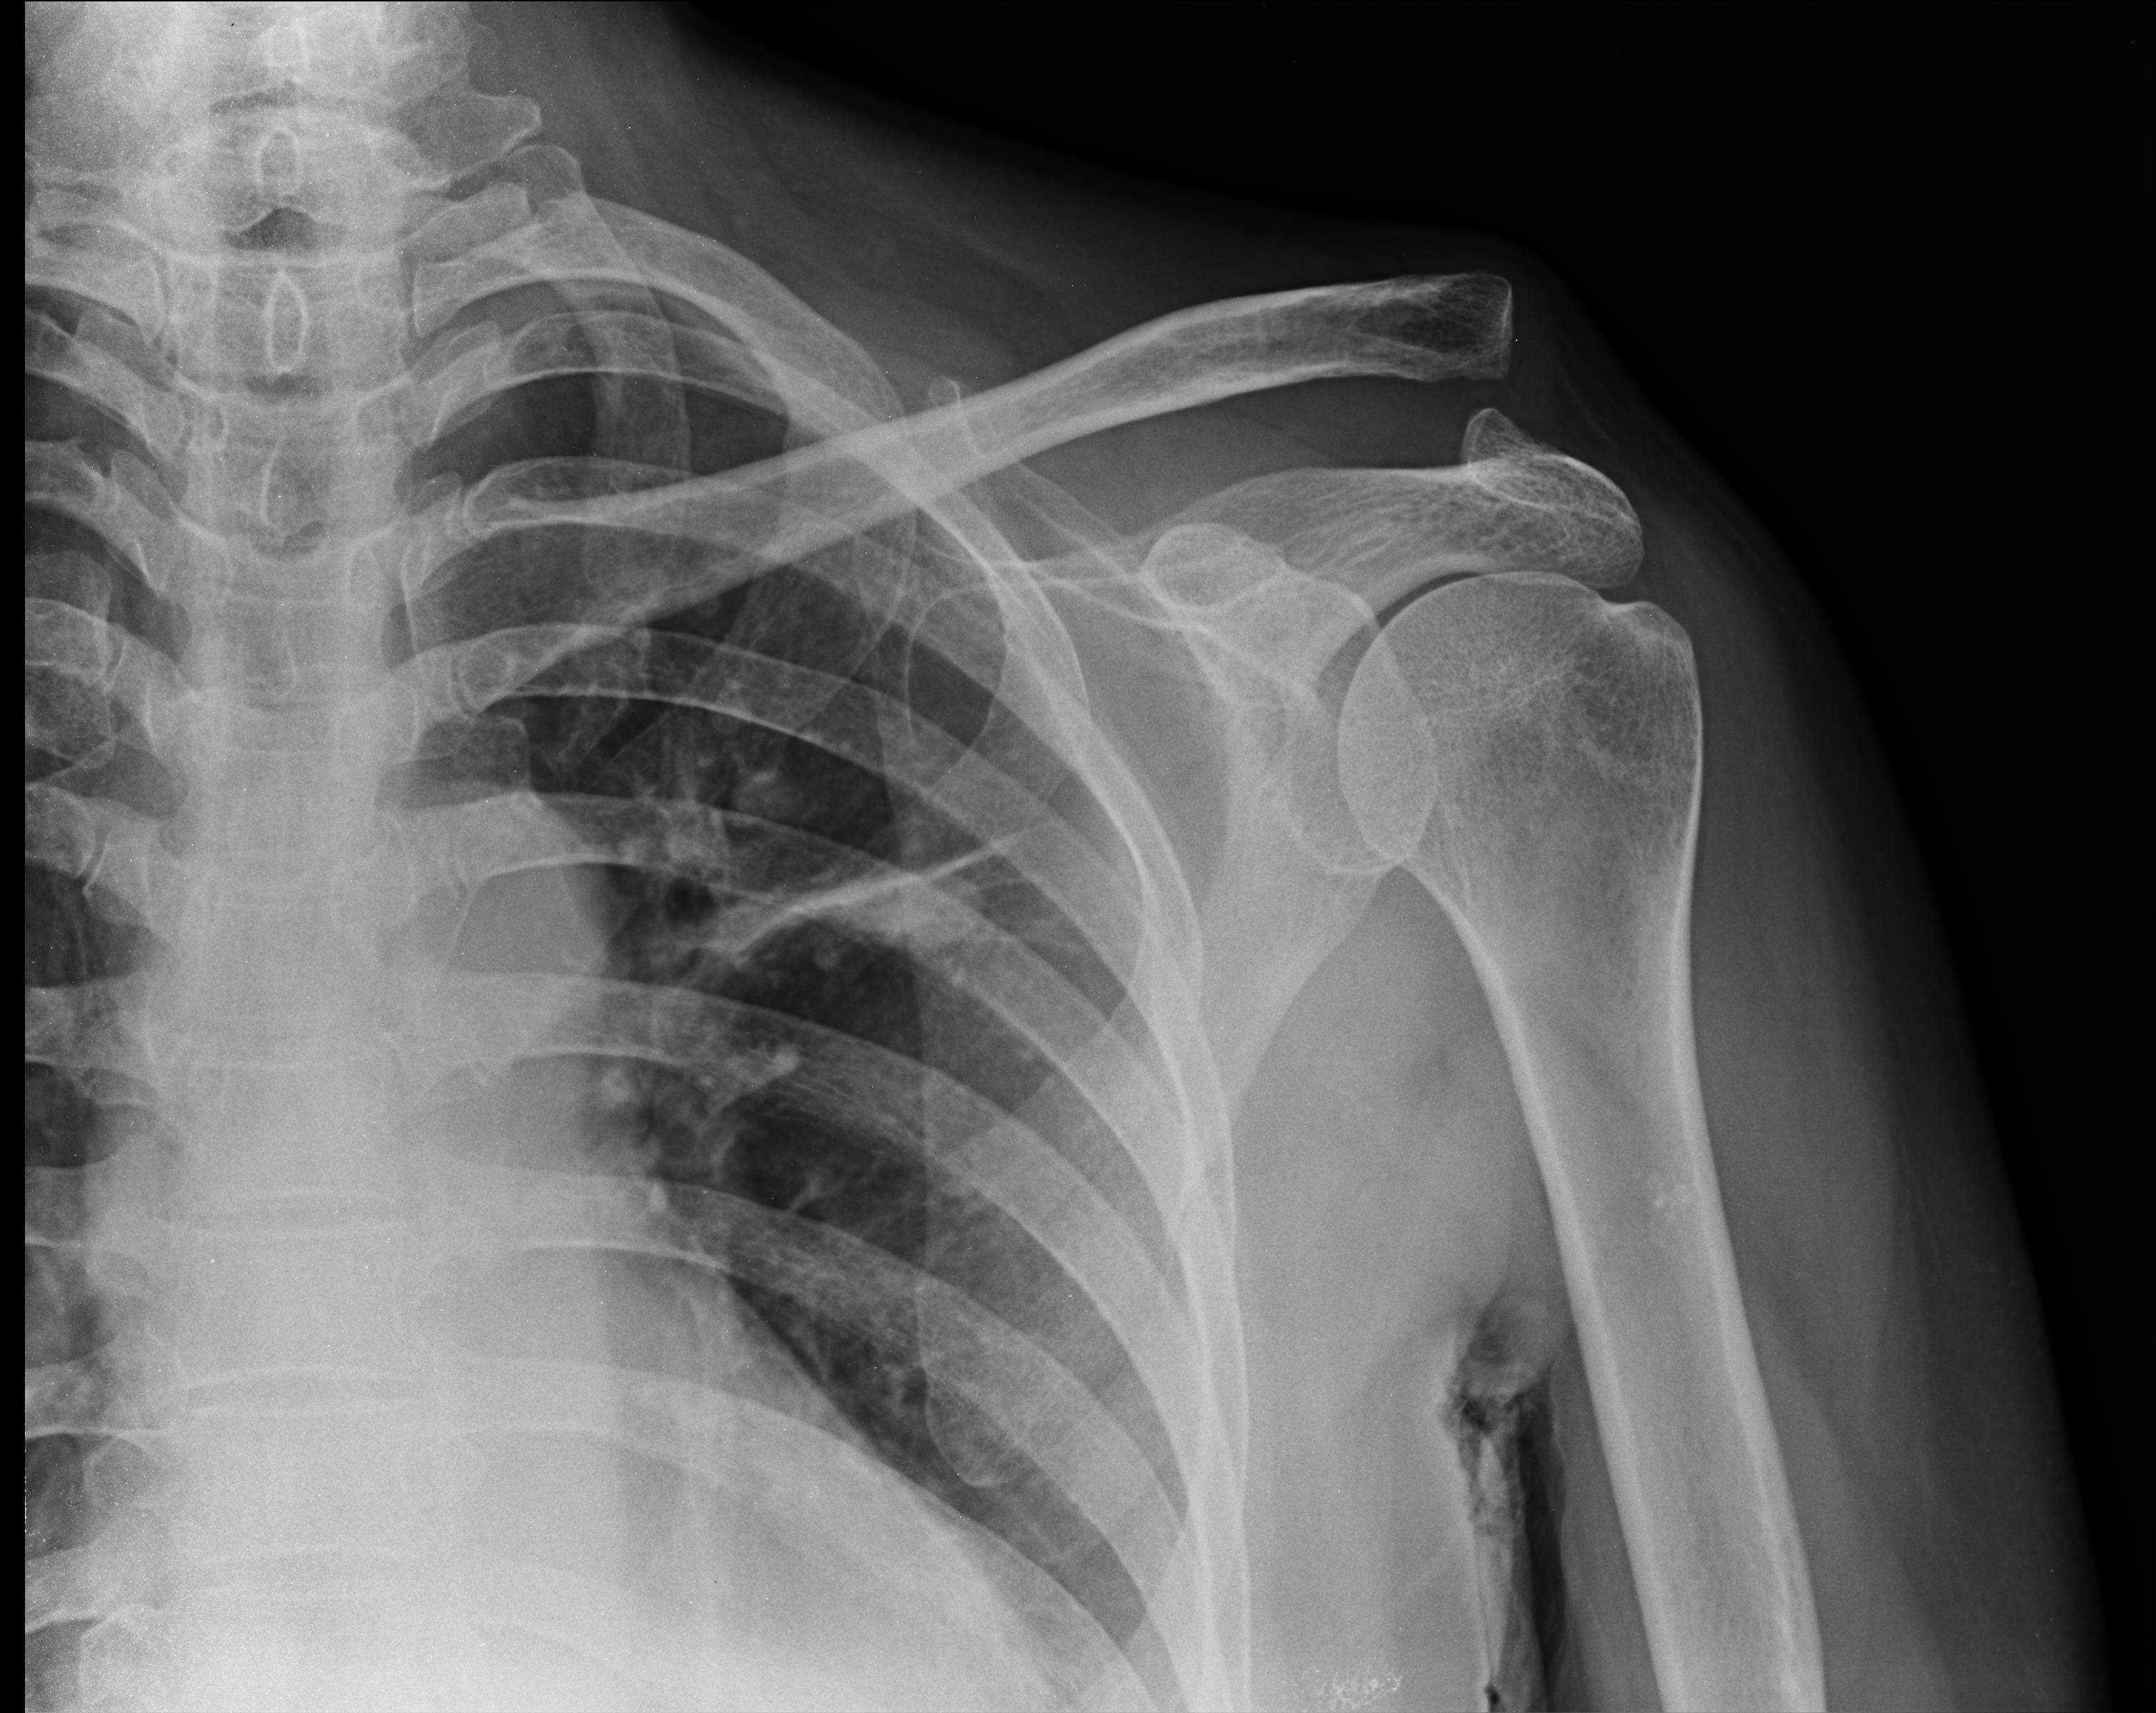

X-ray Wallpapers - Top Free X-ray Backgrounds - WallpaperAccess

wallpaperaccess.comray acromioclavicular radiology separated radiopaedia rays dislocation knochenkrebs grafi radiologie injury clavicola ursachen typen symptome krebs radiografia quiz medicare dores

wallpaperaccess.comray acromioclavicular radiology separated radiopaedia rays dislocation knochenkrebs grafi radiologie injury clavicola ursachen typen symptome krebs radiografia quiz medicare dores